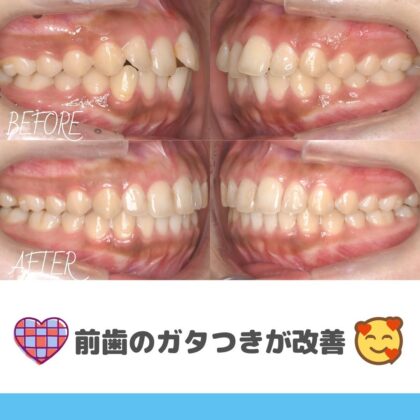

2025.12.18

年齢 9歳 主訴 前歯が出ている、がたつきが気になる 治療...